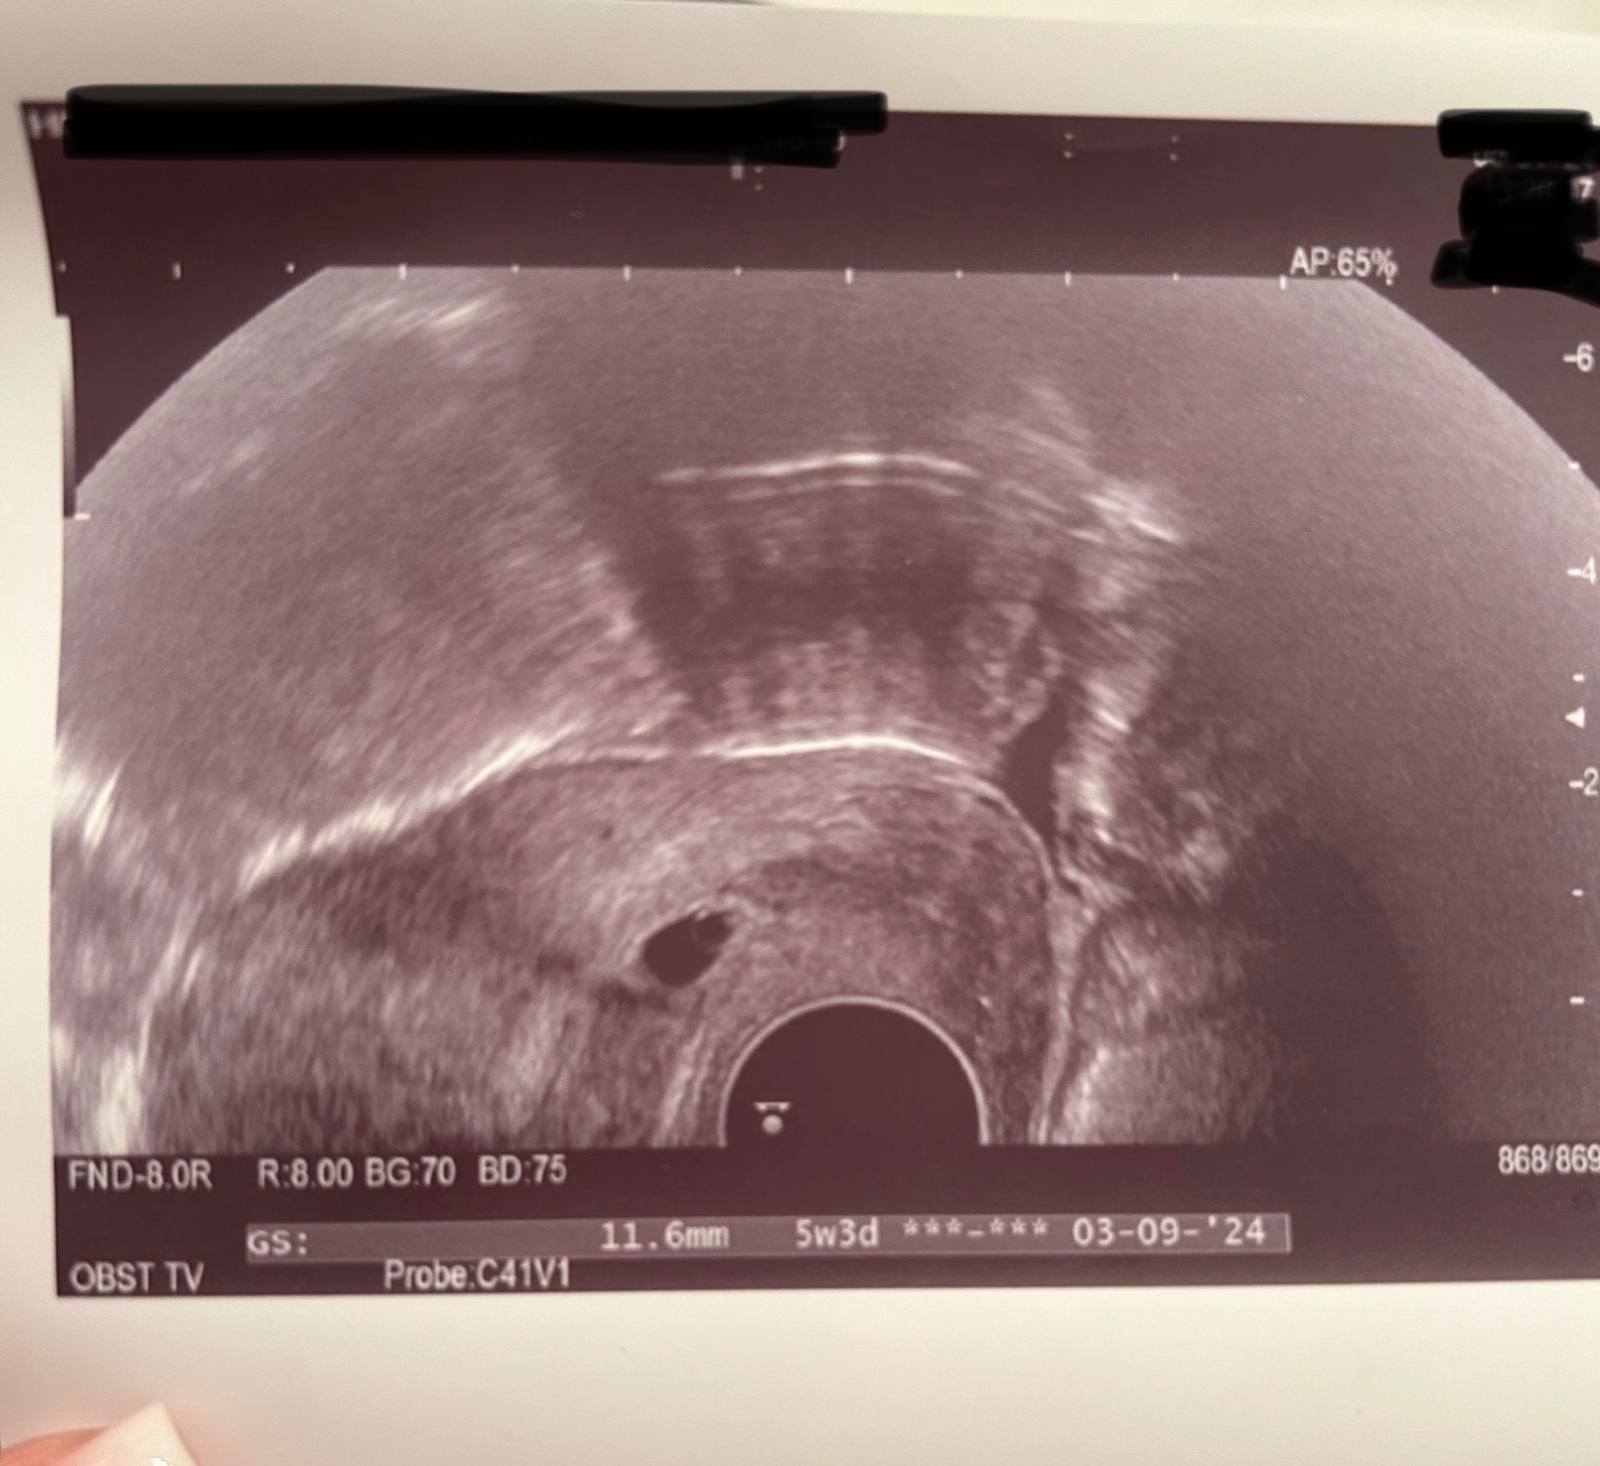

@vanoce2023 no jen je zajímavé že vaše DR nic neviděla když jste už u ní měla bejt 5+4tt a zde se píše 5+3 tím pádem jste tam byla brzo jinak podle ultrazvuku to zatím vypadá že by to mohlo bejt na dobre cestě zas úplně nahoru jít nemusí tam půjde až časem někdy to doktoři hned vidí vše špatně

Ve středu jsem měla přes 4000 a na UTZ je to 5+4, tak nevím proč to tak je. V pátek jsem měla přes 5000.